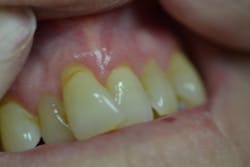

Figure 3: Maxillary anterior right

Her periodontal probing depths ranged from 2 mm to 6 mm, with as much as 4 mm of recession noted in some areas. Tooth No. 19 had a fractured off DL cusp to the gumline with decay close to the nerve; No. 29 had deep DO decay that would require endodontic treatment, buildup, and a crown to repair or possibly extraction; and No. 31 was unrestorable with buccal decay to the nerve, through the furcation, and at the bone level (figures 1–6). Faced with that treatment plan, she would also need four quads of scaling and root planing with anesthetic. We were able to coordinate the schedule to extract No. 31 directly after her periodontal treatment while she was still anesthetized.